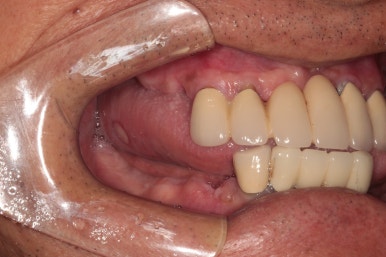

측면 사진입니다.

먼저 왼쪽 사진이 환자분의 우측 사진인데요, 아래턱 어금니 부위는 이미 치아가 없어진지 오래되어 깔끔하게 나은 잇몸상태를 볼 수 있었습니다.

위쪽은 치석이 너무 많았습니다. 만성 치주염이 심하신 상태였죠..

오른쪽 사진이 환자분의 좌측 사진입니다. 여기서 잘 안보이실 수 있지만, 왼쪽 아래 송곳니 부위에 잇몸 속 고름이 잔뜩 차서.. 흔들흔들한 상태였어요.